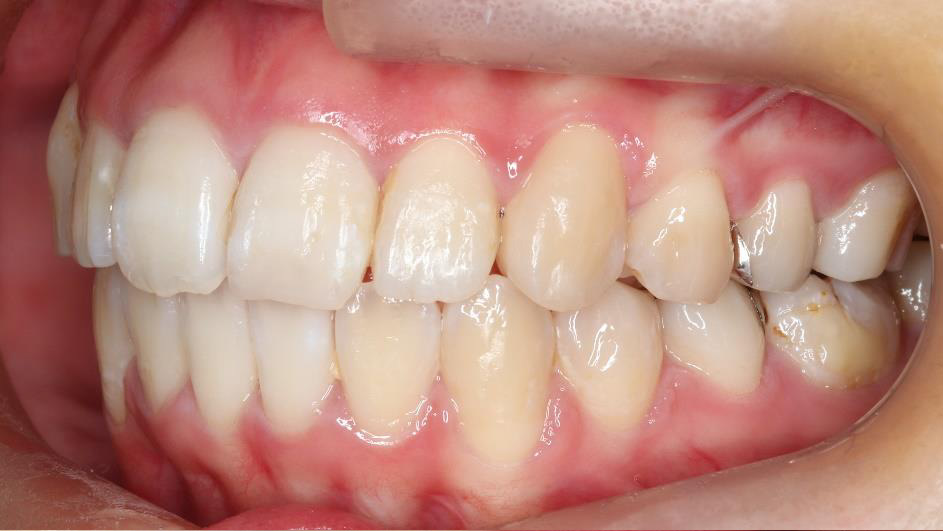

上顎前突といわれ、上顎の前歯が唇側に出ている状態を言います。

前歯が出ることで見た目の問題もありますが、口を閉じることができない、口呼吸をしてしまう、外傷などのリスクがあります。

日本人に叢生の次に多い不正咬合と言われており、自然に治ることはありません。また上の前歯が出ている事だけが気になるかもしれませんが、多くの場合、上顎の奥歯の位置に問題があることが多く、部分矯正でなく根本的な治療をした方がいい場合が殆どです。

口を閉じることができないことで、鼻呼吸でなく口呼吸をしてしまい、結果、成長期の場合顎の骨の成長を邪魔してしまうとも言われております。その他、口呼吸はアトピーなどを含むアレルギー症状の悪化、風邪を含むウイルス性の感染症にかかりやすいなどのリスクも増大してしまいます。

歯並びだけでなく全身への影響も多い為、早期の治療をおすすめ致します。